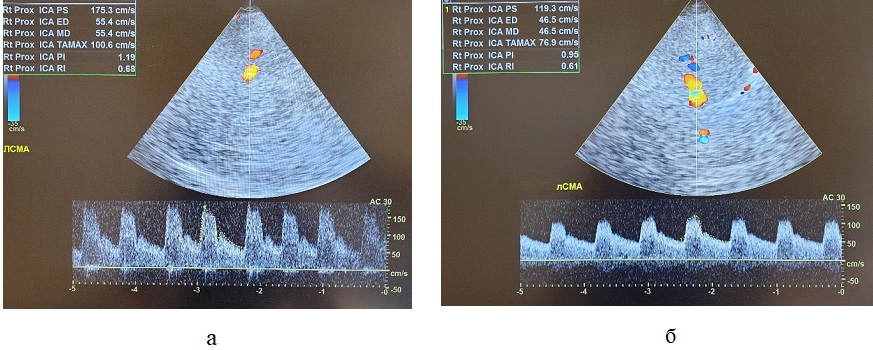

Рисунок 6 - Пациент Л., 73 лет, с ишемическим инсультом после тромболитической терапии, осложнившейся геморрагической трансформацией очага ишемии. Транскраниальное дуплексное сканирование артерий головного мозга через височное окно

Примечание: а – Первые сутки после тромболитической терапии: синдром гиперперфузии в виде ускорения пиковой систолической скорости кровотока до 175 см/с и усредненной по времени максимальной скорости кровотока (TAMAX) до 101 см/с в левой СМА у пациента с геморрагической трансформацией очага ишемии; б – 7-е сутки после тромболитической терапии: скоростные показатели в пределах нормативных значений – пиковая систолическая скорость кровотока 119 см/с, усредненная по времени максимальная скорость кровотока (TAMAX) 77 см/с в левой СМА у пациента с геморрагической трансформацией очага ишемии.